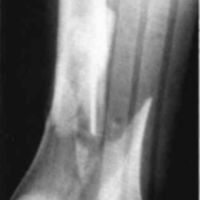

A nineteen year old male sustained a distal fracture with a split condylar fracture to the right leg (Fig. 10) and a lateral condyle fracture on the contralateral side (Fig. 11). Fractures were stabilized, but were not internally fixed at time of admission because of emergency vascular repairs being required. Three days post injury, the patient underwent ORIF of his fractures (Fig. 12 and Fig. 13). The right leg was placed in a free knee Mobilizing Brace and the left leg was placed in the rehabilitative free knee orthosis. A continuous passive motion dynamic suspension system was placed on the lower right extremity (Fig. 14). The lower left extremity had normal pain free motion following surgery. The patient was kept in passive motion for five days and achieved 0-100° of pain free motion. A cast brace was applied on the right extremity; the patient received gait training and was discharged.

Figure 10:

Figure 11: